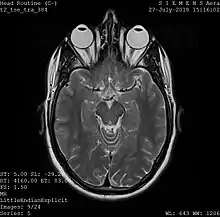

One frame of an MRI scan of the head showing the eyes and brain

A magnetic resonance imaging instrument (MRI scanner), or "nuclear magnetic resonance (NMR) imaging" scanner as it was originally known, uses powerful magnets to polarize and excite hydrogen nuclei (i.e., single protons) of water molecules in human tissue, producing a detectable signal which is spatially encoded, resulting in images of the body.[5] The MRI machine emits a radio frequency (RF) pulse at the resonant frequency of the hydrogen atoms on water molecules. Radio frequency antennas ("RF coils") send the pulse to the area of the body to be examined. The RF pulse is absorbed by protons, causing their direction with respect to the primary magnetic field to change. When the RF pulse is turned off, the protons "relax" back to alignment with the primary magnet and emit radio-waves in the process. This radio-frequency emission from the hydrogen-atoms on water is what is detected and reconstructed into an image. The resonant frequency of a spinning magnetic dipole (of which protons are one example) is called the Larmor frequency and is determined by the strength of the main magnetic field and the chemical environment of the nuclei of interest. MRI uses three electromagnetic fields: a very strong (typically 1.5 to 3 teslas) static magnetic field to polarize the hydrogen nuclei, called the primary field; gradient fields that can be modified to vary in space and time (on the order of 1 kHz) for spatial encoding, often simply called gradients; and a spatially homogeneous radio-frequency (RF) field for manipulation of the hydrogen nuclei to produce measurable signals, collected through an RF antenna.

Like CT, MRI traditionally creates a two-dimensional image of a thin "slice" of the body and is therefore considered a tomographic imaging technique. Modern MRI instruments are capable of producing images in the form of 3D blocks, which may be considered a generalization of the single-slice, tomographic, concept. Unlike CT, MRI does not involve the use of ionizing radiation and is therefore not associated with the same health hazards. For example, because MRI has only been in use since the early 1980s, there are no known long-term effects of exposure to strong static fields (this is the subject of some debate; see 'Safety' in MRI) and therefore there is no limit to the number of scans to which an individual can be subjected, in contrast with X-ray and CT. However, there are well-identified health risks associated with tissue heating from exposure to the RF field and the presence of implanted devices in the body, such as pacemakers. These risks are strictly controlled as part of the design of the instrument and the scanning protocols used.

Because CT and MRI are sensitive to different tissue properties, the appearances of the images obtained with the two techniques differ markedly. In CT, X-rays must be blocked by some form of dense tissue to create an image, so the image quality when looking at soft tissues will be poor. In MRI, while any nucleus with a net nuclear spin can be used, the proton of the hydrogen atom remains the most widely used, especially in the clinical setting, because it is so ubiquitous and returns a large signal. This nucleus, present in water molecules, allows the excellent soft-tissue contrast achievable with MRI.[6]